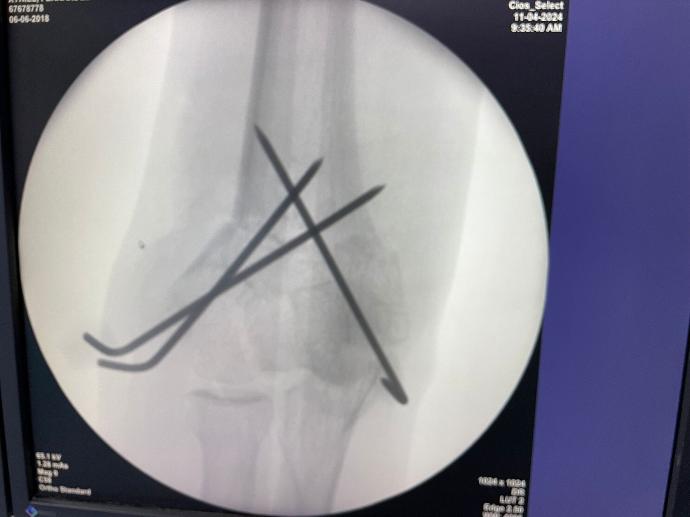

個案 1:

12 歲女孩 右側手肘骨折後變形

手術前位置

手術矯正後手肘恢復正常位置

手術中拍的 X-ray